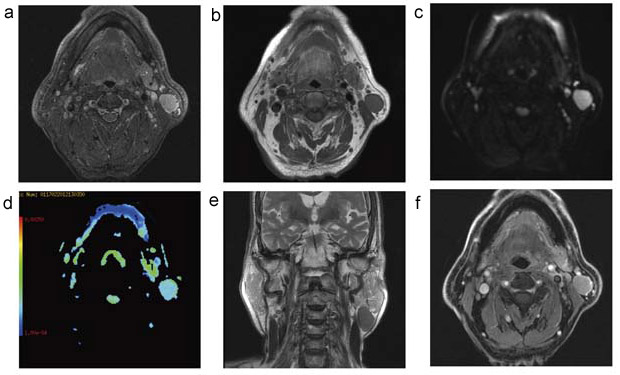

まずは,耳下腺下極のワルチン腫瘍である(図3)。STIR,SE法T1強調画像,拡散強調画像,T2強調画像,脂肪抑制Gd-DTPAダイナミック造影検査が行われている。下顎周囲においても均一な脂肪抑制効果が得られており,拡散強調画像も高画質である。造影検査における脂肪抑制は,本検査時にはLAVA-FLEXを選択している。LAVA-FLEXは,体幹部で有用とされているシーケンスであるが,その他の領域にも広く応用可能であることがわかる。FLEX(LAVA-FLEX,VIBRANT-FLEX)も後述するIDEALも,フィールドマップを利用してピクセルごとの局所磁場不均一を計算し再構成するアプリケーションであり,FLEXの場合,ダイナミック撮像はもちろん,息止め時や乳腺領域にも使用可能である。

図3 左耳下腺下極のワルチン腫瘍

a:STIR軸位断像 /

b:T1強調画像軸位断像 /

c:拡散強調画像軸位断像(b値1000)

d:ADC map /

e:T2強調画像冠状断像 /

f:LAVA-FLEXによる脂肪抑制造影T1強調画像軸位断像